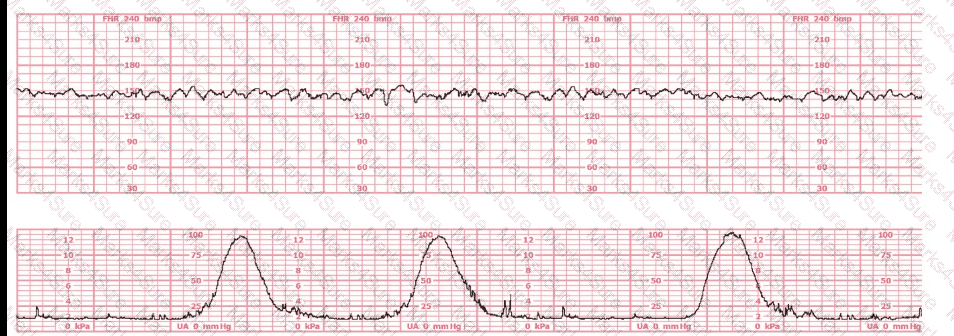

A woman is being induced with oxytocin. The tracing shown is representative of 20 minutes. Based on this tracing, the next step would be to: